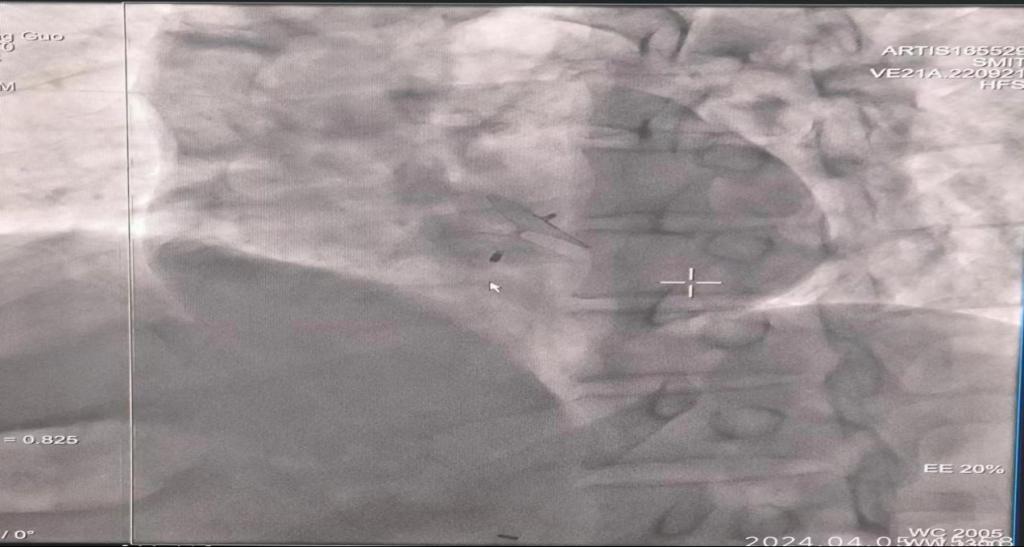

患者,男性,反复出现头晕、头痛、手脚麻木等症状,近1月症状加重,头痛频繁,行食道超声和心脏彩超等相关检查后,提示患有卵圆孔未闭。经主任医师崔松教授会诊后,建议行卵圆孔封堵术。术中将导管及导丝经未闭的卵圆孔送入左心房,将卵圆孔未闭封堵器通过鞘管送至左心房,释放卵圆孔未闭封堵器,封堵器在房间隔的两侧扩张成型。患者术后生命体征良好,头晕症状消失,后痊愈出院。

经导管介入封堵术是一种在局麻下进行的微创手术,手术过程中患者是清醒的,具有痛苦小、恢复快的特点。一般术后12~24小时就可以下床活动。其原理是通过大腿根部的股静脉将一根导管送入右心房,穿过未闭卵圆孔至左心房,释放专用封堵器,进而关闭卵圆孔,从而达到根治的目的。但介入封堵术并不适用于所有患者,具有严格的适应证及禁忌证要求,行封堵术前医生会进行全面评估,在征求患者的意见后进行。行封堵术后,患者需遵医嘱定期至医院复查,主要需要通过复查超声心动图了解心脏结构、封堵器位置及有无封堵器血栓等。封堵卵圆孔术目前未发现严重的并发症。